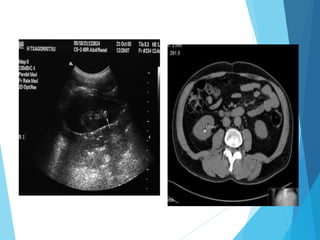

dudoso: TC

o ecografía

(niños y

jóvenes)

 Ecografía es el estudio de

primera elección en Dx de

afecciones de vesícula y

vías biliares, además la,

gammagrafía, TAC…